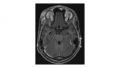

Extraocular findings include lid granulomas and inflammation, lesions of the orbit, optic nerve granulomas and atrophy, and cranial nerve paralysis.[1] Abducens nerve paralysis specifically has been seen as a complication of central nervous system coccidioidomycosis, likely secondary to increased intracranial pressure.[10] Figure 1 shows a magnetic resonance imaging (MRI) of osteomyelitis from Coccidioidomycosis in the superotemporal orbital rim.